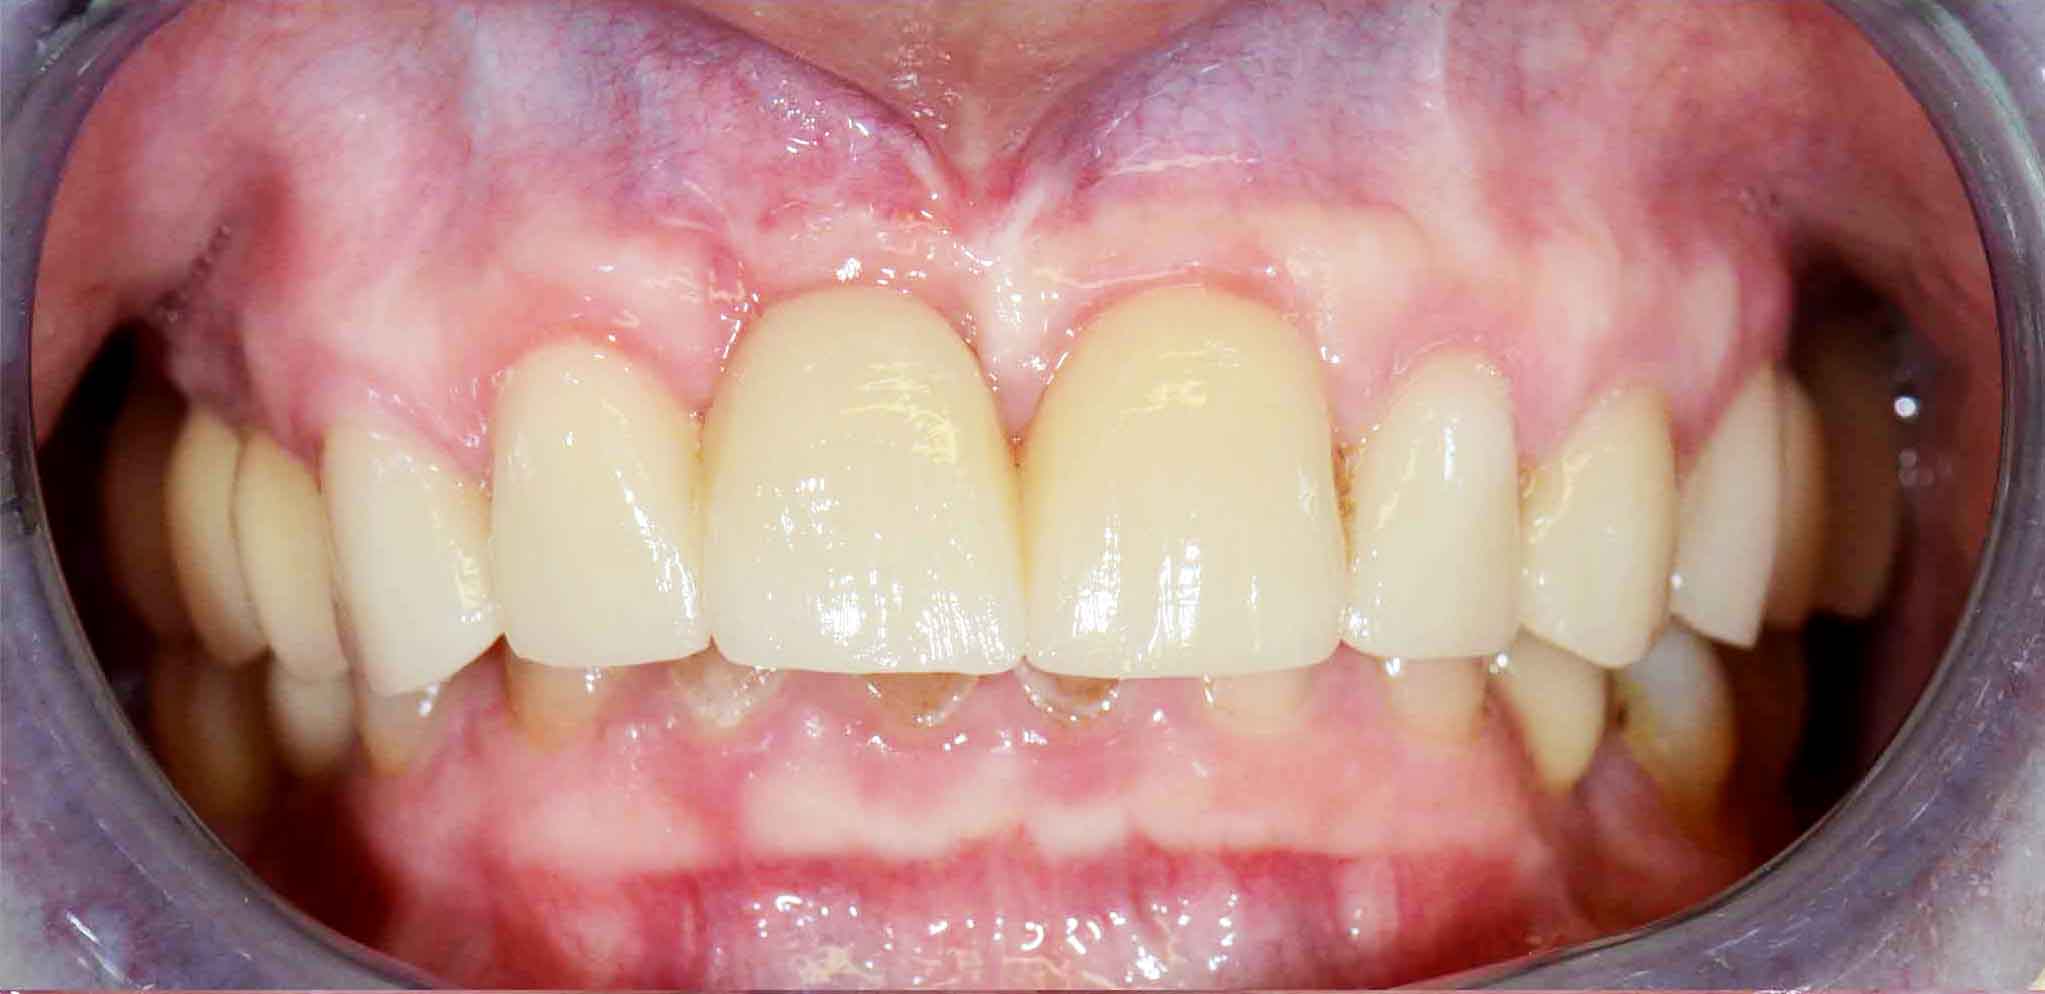

Finalizou-se com colocação de Coroas Cerâmicas.

Reabilitação Estética com Coroas e Facetas Cerâmicas.

Opção por recobrimento dentário com coroas nos dentes mais destruidos e de facetas naqueles menos atingidos evitando desgastes muito agressivos.